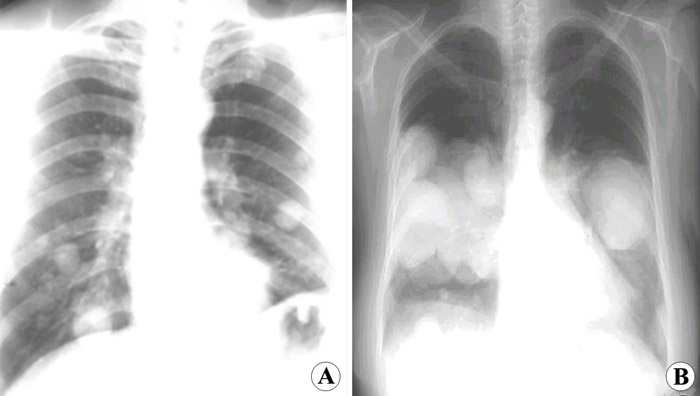

2014年实践技能医师医学影像学:肺转移癌X线图